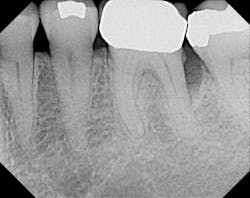

X-ray before.

X-ray six months after postop. Regeneration using laser, Emdogain, and DFDBA (Demineralized Freeze-Dried Bone Allograft).Erbium lasers are powerful tools that give the clinician the ability to achieve predictable periodontal regeneration, enhance the surgical experience for the clinician, and create a more pleasant healing experience for the patient.It is important to understand that a laser does not replace sound biology, science, and diagnostics. Lasers are not magical. It is foolish to think that you can take a laser light, direct it into a patient’s periodontal pocket, and expect a supernatural result. As with anything else, one must attain extensive training in the use of lasers, and use sound clinical judgment prior to applying laser technology into patient care. Author bioMark Schlesinger, DDS, is a diplomate of the American Board of Periodontology and a clinical assistant professor in the Department of Periodontics and Implant Dentistry at the New York University College of Dentistry. You may contact him at The Diamond Schlesinger Group, nyimplantdentistry.com or nylaserinstitute.com.